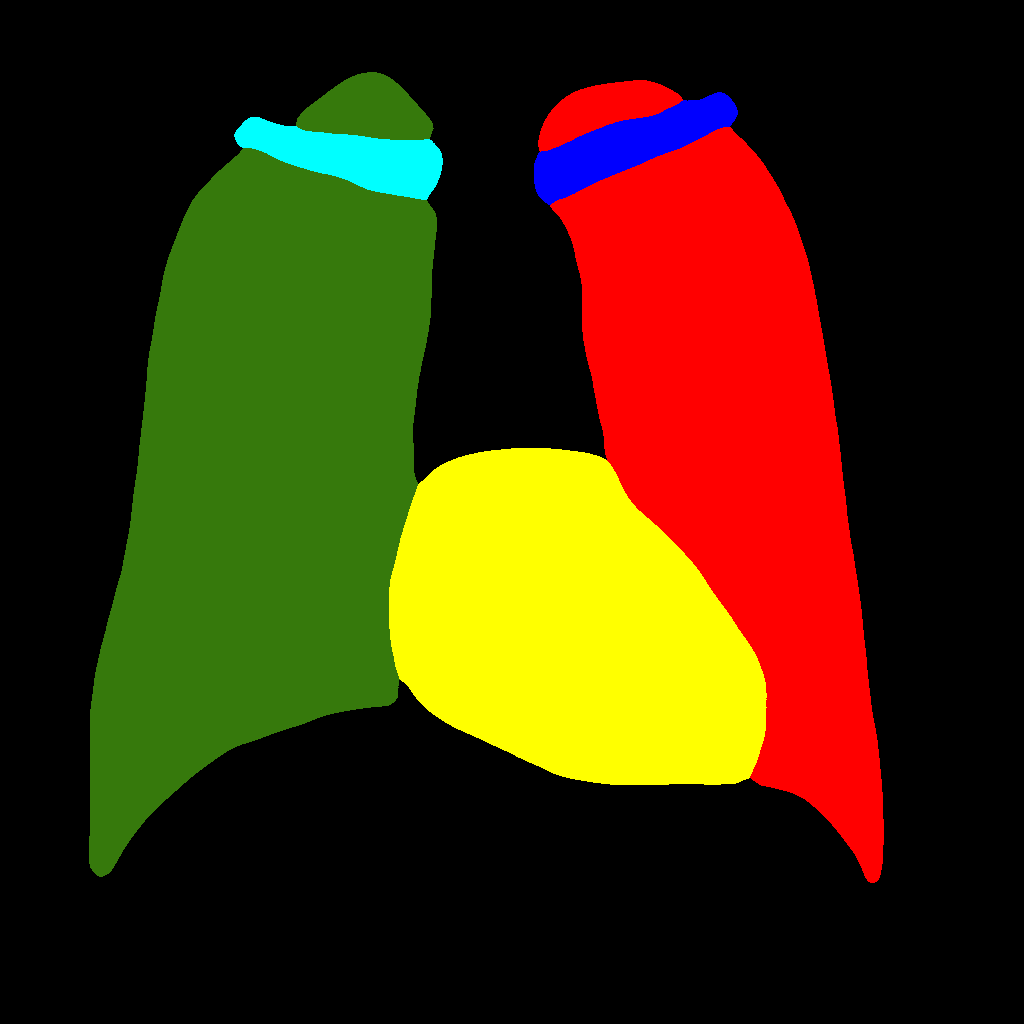

It consists in further subdividing the generation procedure, with a first phase consisting in generating the position and type of the objects that will be generated later, regardless of their shape or appearance. This is obtained by generating label–maps that contain “dots” in correspondence with different anatomical parts (lungs, heart, clavicles). The dots can be considered as “seeds”, from which, through the subsequent steps, the complete label–maps are realized (second phase). Finally, in the last step, chest X–ray images are generated from the label–maps. The exact procedure is described in the following. Initially, label–maps containing “dots”, with a specific value for each anatomic part, are created. The position of the “dot” center is given by the centroid of each labeled anatomic part. The label–maps generated in this phase have a low resolution (), as a high level of detail is not necessary, being the exact object shapes not defined — but only their centroid positions. It should be observed that this also allows to significantly reduce the computational burden of this stage and speedup the computation. The generated label–maps must be subsequently resized to the original image resolution — required in the following stages of generation (a nearest neighbour interpolation has been used to maintain the original label codes) — and translated into labels, which will be finally translated into images, using Pix2PixHD (see Figure 3).